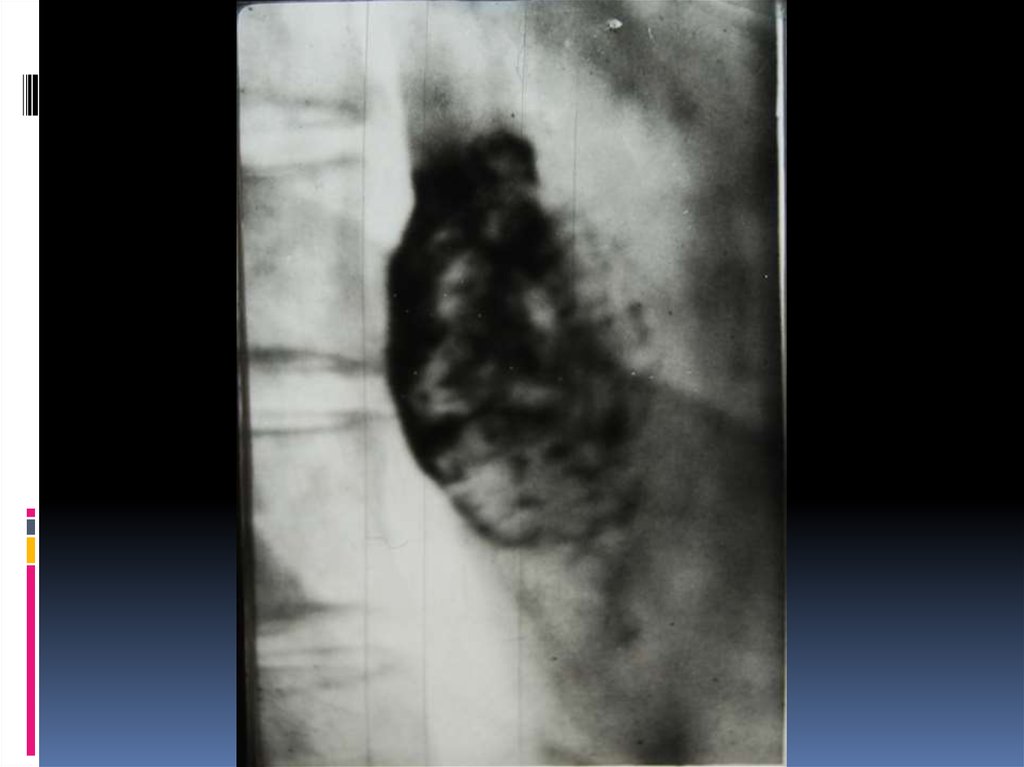

16. Рентгенодиагностика рака желудочно-кишечного тракта

Рентгенодиагностика

рака желудочнокишечного тракта

17. Классификация рака органов ЖКТ

1. Экзофитная форма:

2. Эндофитная форма:

узловая форма;

диффузноинфильтративная

форма;

полипоподобная

чашеподобная форма. инфильтративноязвенная.

3. СМЕШАННАЯ ФОРМА – 10-15%